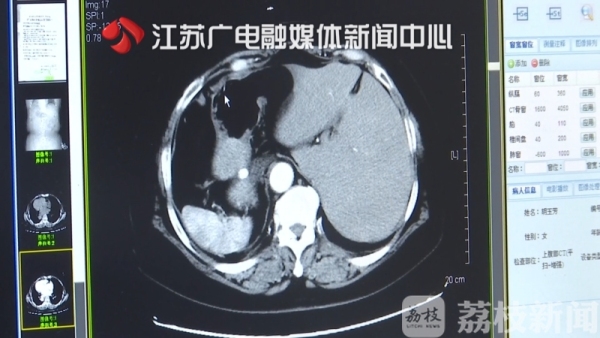

结果出来后,医生惊讶地发现,胡老太太的五脏六腑竟然全长反了。

正常的胆结石患者都是右腹疼痛,这位病人的位置却是反的,会不会还存在其他病情?随后医生给胡老太太做了B超检查。